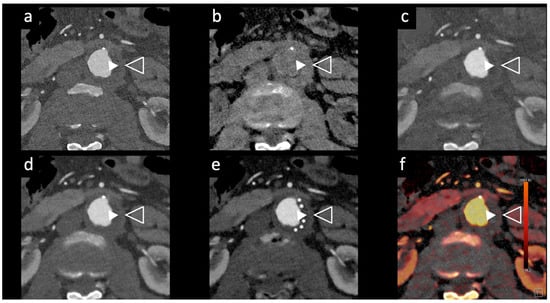

Figure 5. Aortic angiographic evaluation of the abdominal aortic aneurysm evaluated with photon-counting CT and standard contrast media (the same example of Figure 2, coronal view). The aortic wall is indicated between solid and empty arrowhead. 3D-Volume Rendering representation (a); High-Resolution coronal evaluation, 55 keV, Kernel Bv68 Q4 Matrix 1024 (b); Spectral Dual Energy coronal Reconstruction (c). Department of Radiology, Fondazione Toscana Gabriele Monasterio, Pisa, Italy.

Rau et al. [14] presented a case study of an 81-year-old patient with incipient chronic renal failure who required contrast-enhanced aortoiliac CT angiography for follow-up imaging of an asymptomatic abdominal aortic aneurysm (AAA). They employed a first-generation PCCT scanner to reduce contrast agent use while maintaining diagnostic reliability. Utilizing a PCCT protocol with dual-source spectral image acquisition and dynamic monochromatic reconstruction near the K-edge of iodine, this study demonstrated a significantly reduced required contrast agent while preserving diagnostic confidence. This study shows promise for minimizing renal damage during imaging. However, further research is needed to refine these protocols and post-processing techniques. A similar case is shown in Figure 2 and Figure 5.